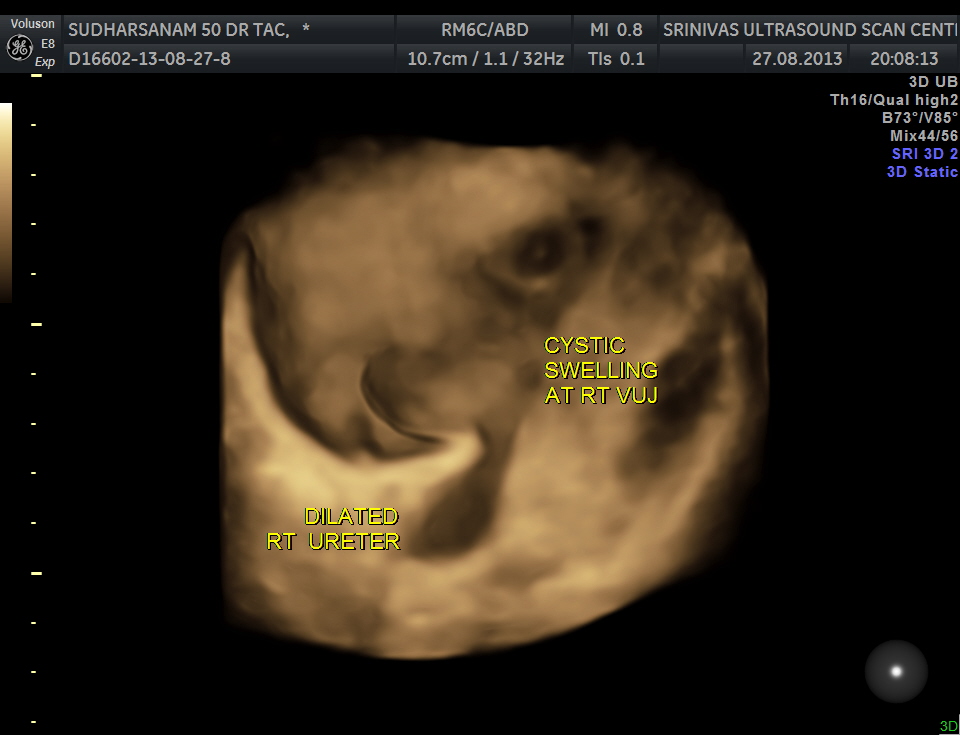

given below are few other reconstructions

The patient was seen by the urologist and an IVP was done , which proved the diagnosis of orthotopic ureterocele . (a ureterocele entirely within the bladder.)

He has been advised cystoscopic surgical correction.